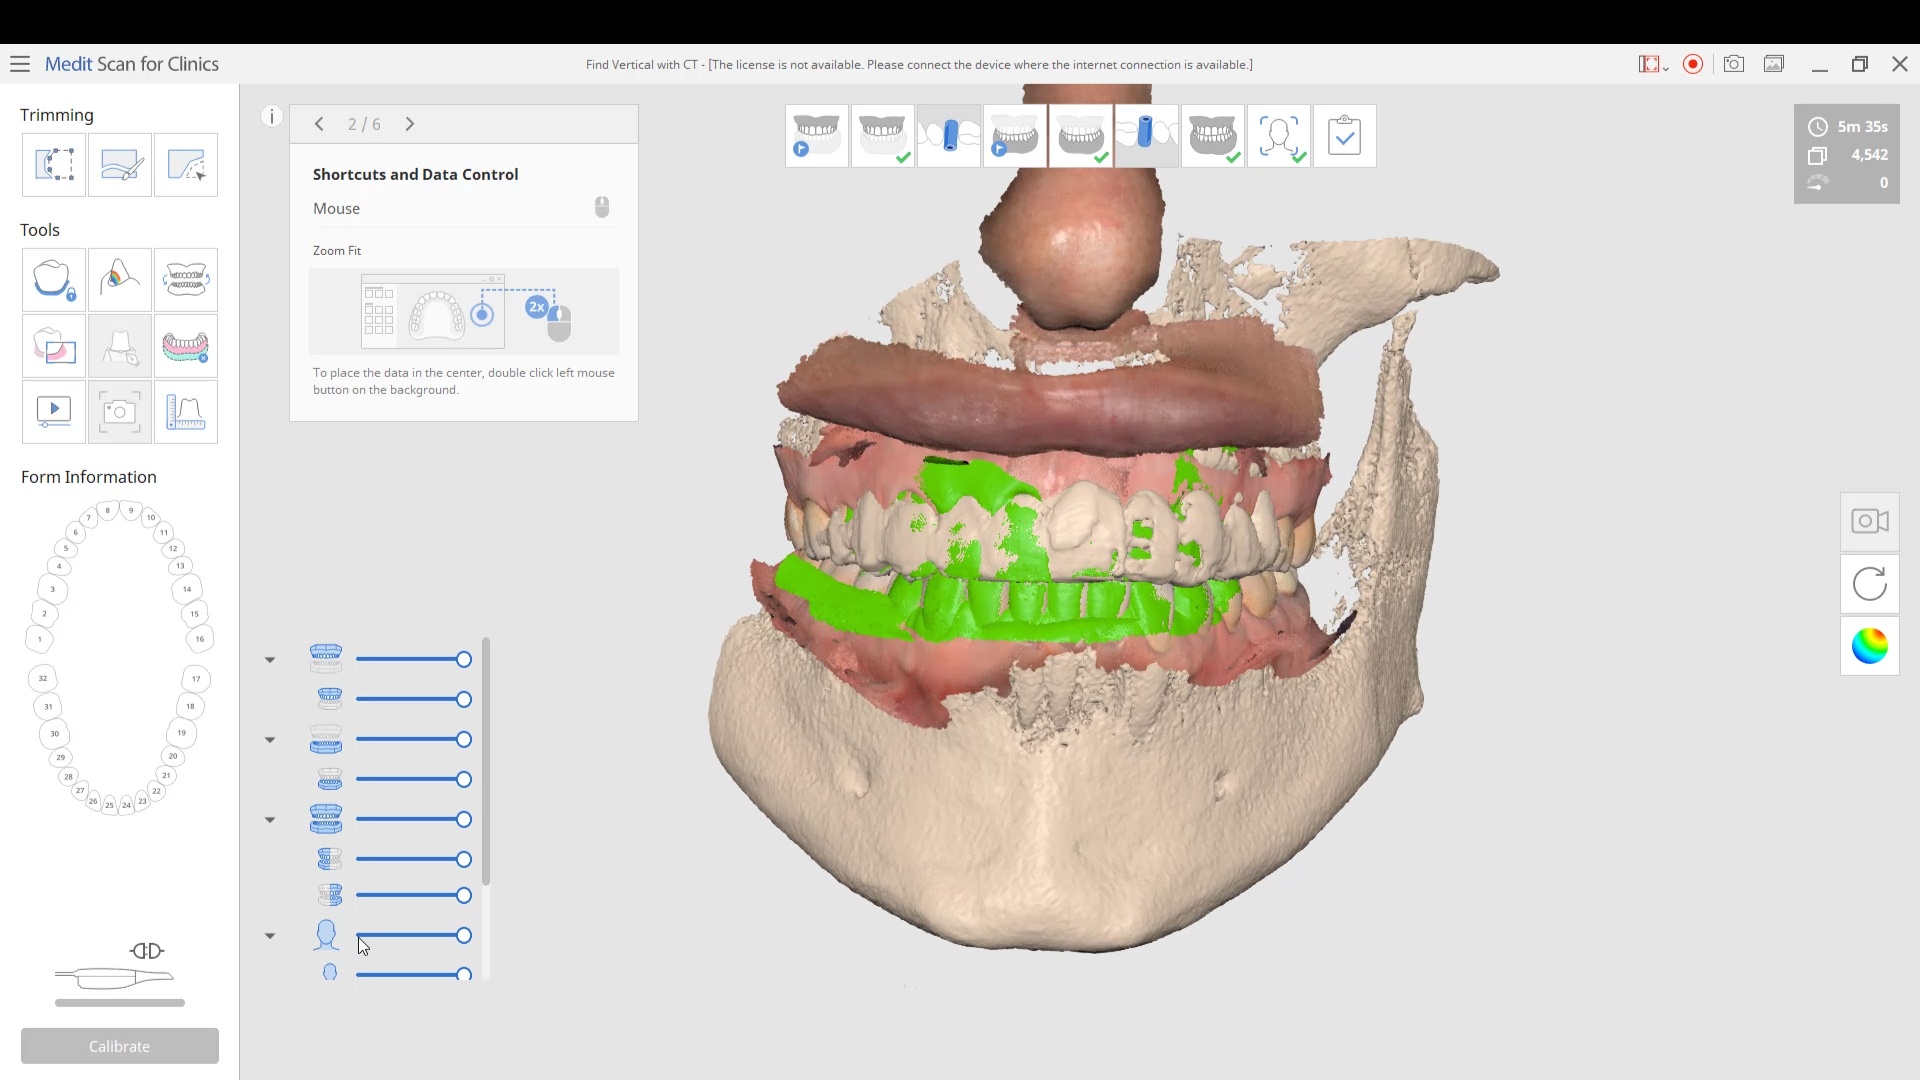

Using the CT as a Remount Jig If You Have Lost The Vertical Dimension For Some Reason or Another

November 20, 2020At CAD-Ray, we have now designed over 20,000 implant cases since 2013. One of the most common requests we get is from doctors doing full arches and their desires to […]